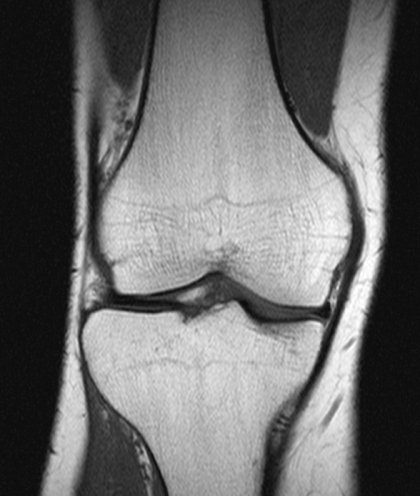

Why do people with knee pain have weak muscles?

Knee pain and knee osteoarthritis are common causes of disability in the UK. They become even more common as people get older. People with knee pain often experience muscle weakness, which can increase disability. Knee pain depends not only on osteoarthritis in the joint, but also on how the central nervous system (CNS: spinal cord and brain) processes nerve signals from the joint. In this study, researchers looked at whether joint disease or changes in the central nervous system cause muscle weakness in people with knee pain.

For more details, visit the summary page

Exploring shared characteristics of different knee pain measurement questionnaires

Knee pain is a common problem across populations. Osteoarthritis or sporting injuries often cause this type of pain. Several treatments are available and more are being developed. There are several questionnaires that measure knee pain and help clinicians or researchers decide whether their proposed treatment works. Although treatments can provide pain relief, such improvement in pain is often not enough to be useful to the person taking the treatment. Despite using treatments, people often continue having unacceptable knee pain.